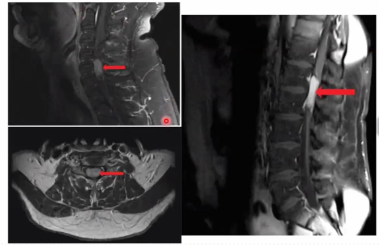

Os Schwannomas são mais comuns em qual segmento da coluna?

Quais as características da imagem?

Cervical > Lombar (Diferente dos meningeomas)

Iso em T1, Hiper no T2, realce de gadolínio em 100%

Imagem em halter (porque passa pelo forame de conjugação, e o dilata)